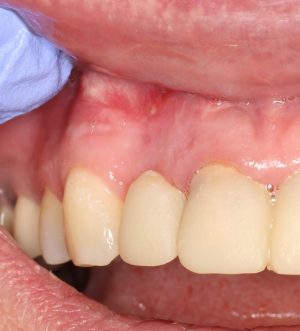

Вот клиническая картина через 4 месяца после ранее проведенной имплантации с остеопластикой:

Как видишь, коллеги из недалекой дружественной страны не осилили снятие швов. Мне это не нравится, хотя и объясняет, почему люди готовы ехать за тыщи километров ради 20-минутной операции удаления зуба мудрости.

Ну хорошо. Швы сняли. Делаем разрез. Обрати внимание, что после всех проведенных операций у нас остается очень небольшой по ширине слой жевательной слизистой оболочки:

Мы встретились как старые друзья. Честно признаюсь, я очень переживал. Я ожидал увидеть какую-нибудь жуть, утраченную кость, периимплантит, разрушенный вхлам протез и всё такое. Но… всё оказалось не так плохо: